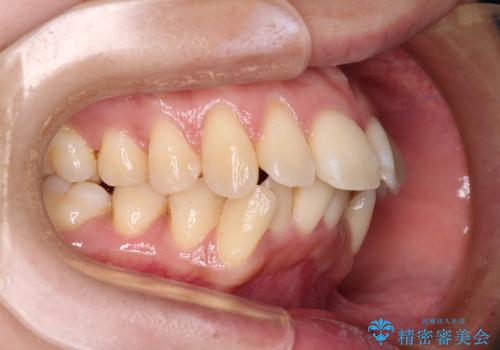

- 前歯の出っ歯と口元の閉じにくさを気にして来院された患者様です。

口元を積極的に引っ込めるために、上下左右の小臼歯4本を抜歯し、目立たないワイヤー装置にて矯正治療を行うこととしました。

上下前歯の歯軸の角度が大きく改善され、お口を閉じたときに顎先に認められた梅干し様の皺も改善されました。